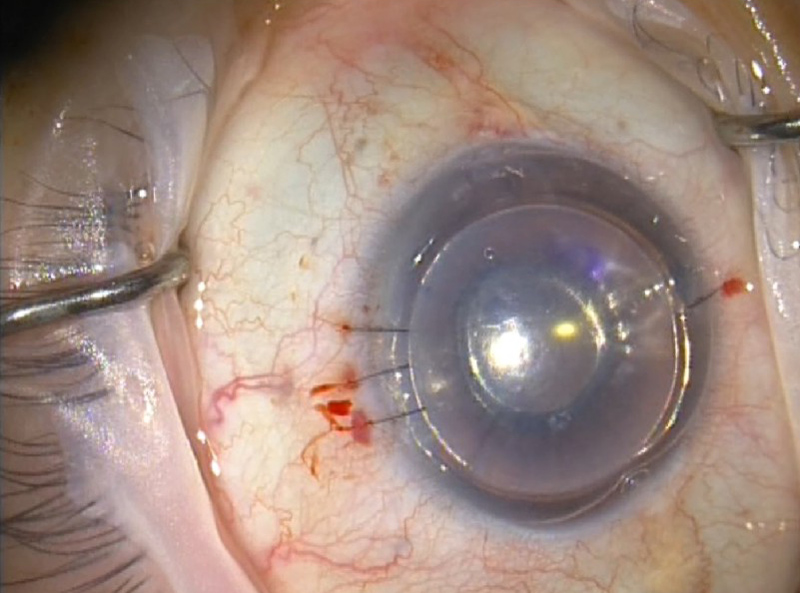

Inserción del PCT en el receptor. El primer paso consiste en una descemetorrhexis de 8.5-9.0 mm, previa realización de una facoemulsificación de cristalino e implante de LIO en ojos fáquicos (Figura 4). Además siempre se ha realizado una iridotomía a las 6 h con vitrectomo si no estaba previamente hecha con láser YAG. La lamela endotelial se ha insertado tirando de ella desde una paracentesis contralateral (técnica de pull-through) (Figura 5). La incisión principal se ha practicado de 5 mm de longitud para no comprimir demasiado el tejido a su paso. La lamela se ha depositado en el insertador de Busin (Figura 6) y la pinza de Tan se ha usado para tirar de ella. Se rellena la cámara con el 90-100% de aire y si a los 20 minutos aproximadamente de reposo en decúbito supino se observa un pequeño menisco de acuoso al poner el paciente en bipedestación no se extrae ninguna cantidad de aire de la cámara anterior (Figura 7).

Figura 4. En el ojo receptor se debe desgarrar la Descemet (descemetorrhexis). La mejor visualización se obtiene mediante el relleno de la CA con burbuja de aire.

Figura 7. Aspecto final de la cirugía. Se deja la cámara anterior totalmente llena de aire. Con la iridotomía inferior se evita el glaucoma por bloqueo pupilar.